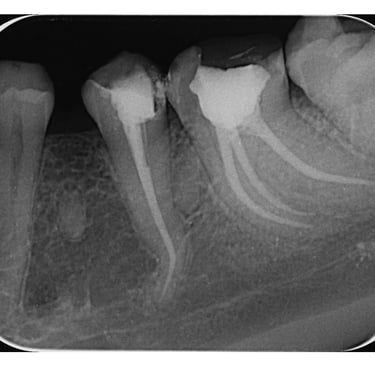

Endodontska terapija, se fokusira na lečenje unutrašnjosti zuba, posebno kanala korena. Savremeni standardi u ovoj oblasti uključuju korišćenje naprednih mašinskih instrumenata, što poboljšava preciznost i efikasnost tretmana.

Mašinska obrada korenovih kanala uključuje upotreba rotacionih ili reciprocirajućih mašina omogućava brže i efikasnije uklanjanje inficiranog tkiva i oblikovanje kanala.

Biokompatibilni materijali: Savremeni materijali za punjenje kanala, kao što su gutaperka ili bioceramika, poboljšavaju dugotrajnost i uspešnost terapije.